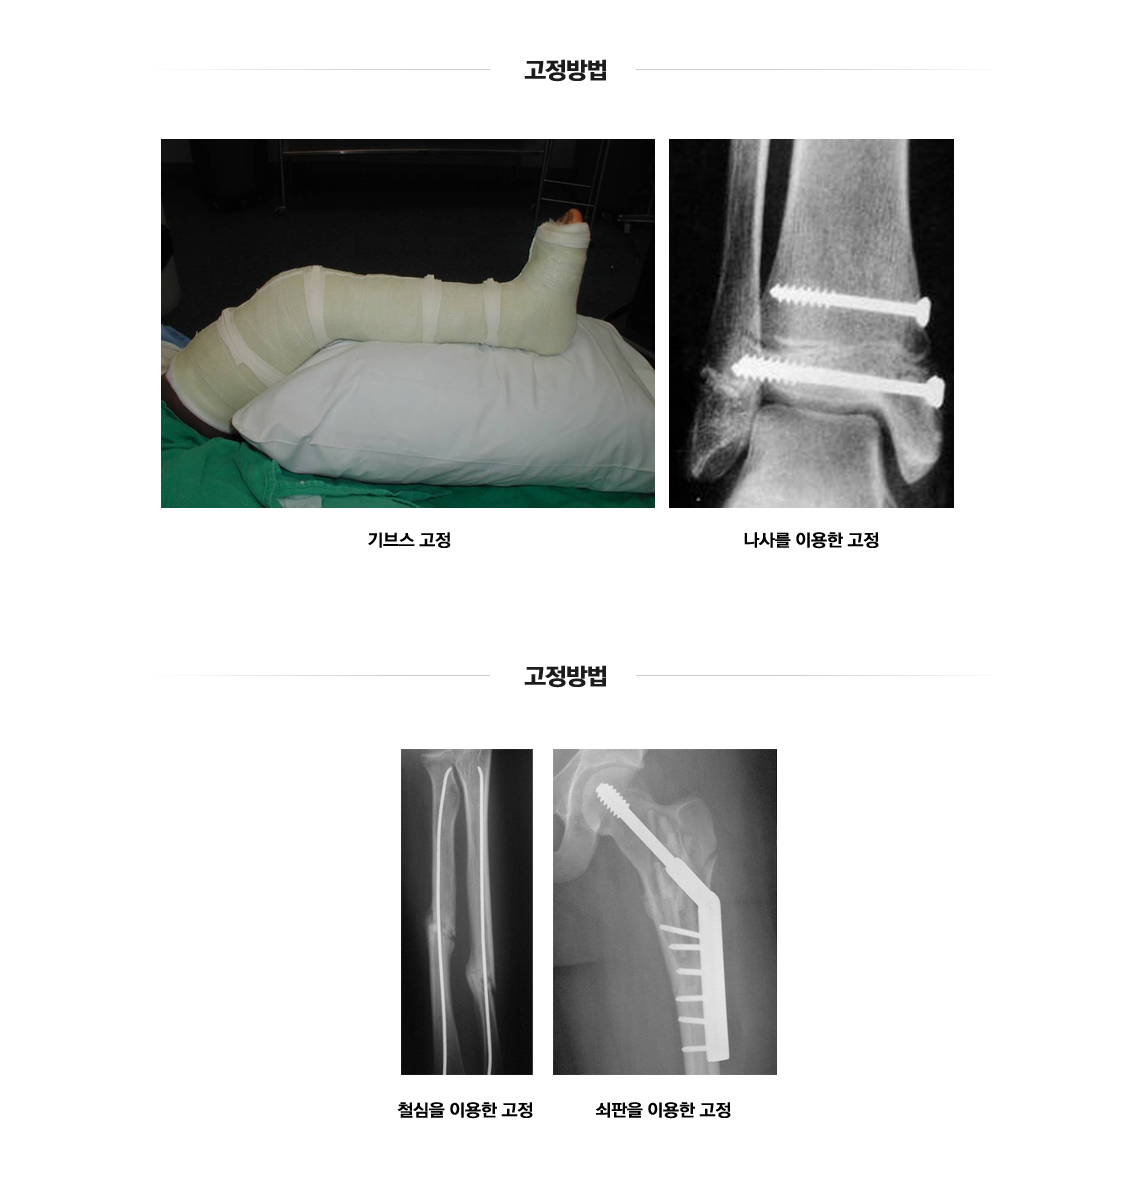

손목골절

관절주위골절(손목)

Fracture